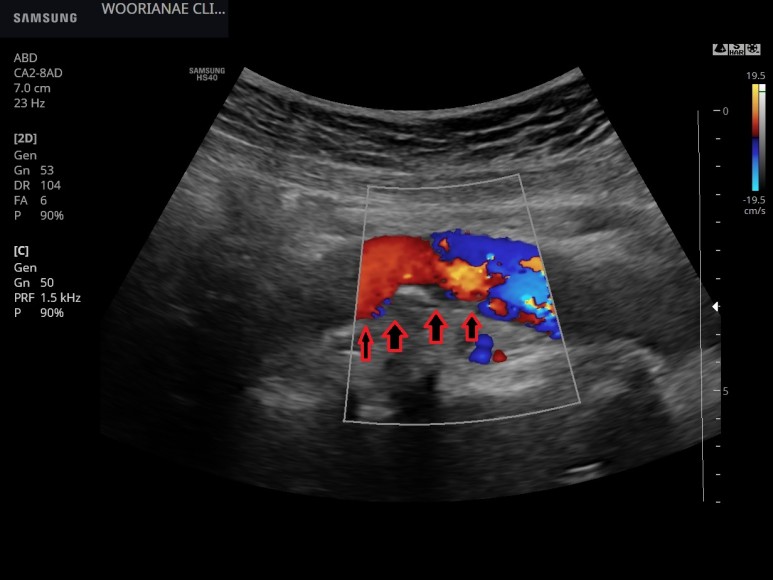

플라크를 흐르는 혈류의 모습

대동맥의 뺨이 쑤시는 등 배제를 위해 혈관도 관찰하지만…명백한 동맥경화, 플라크가 관찰된다; 20대 때부터 흡연력

사슴벌레 모양의 확장 소견(aneu rysmalchange)은 없었고 동맥 주변에 저음영 이상 소견은 관찰되지 않았다.